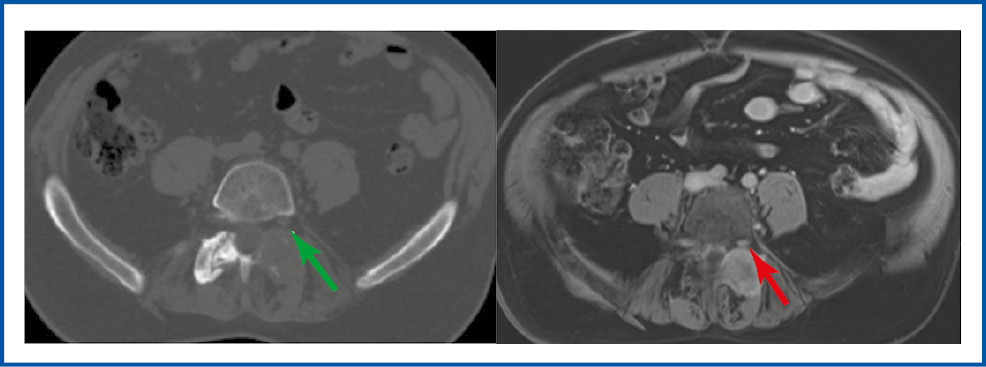

На рис. 4 представлены обследования КТ и МРТ поясничного отдела позвоночника до начала лечения.

Рис. 4. КТ и МРТ поясничного отдела позвоночника больного М. в аксиальном срезе до лечения (стрелками указана компрессия нервного корешка).

Fig. 4. Axial view of CT and MRI of the lumbar spine of the patient M. before treatment (arrows indicate compression of the nerve root).